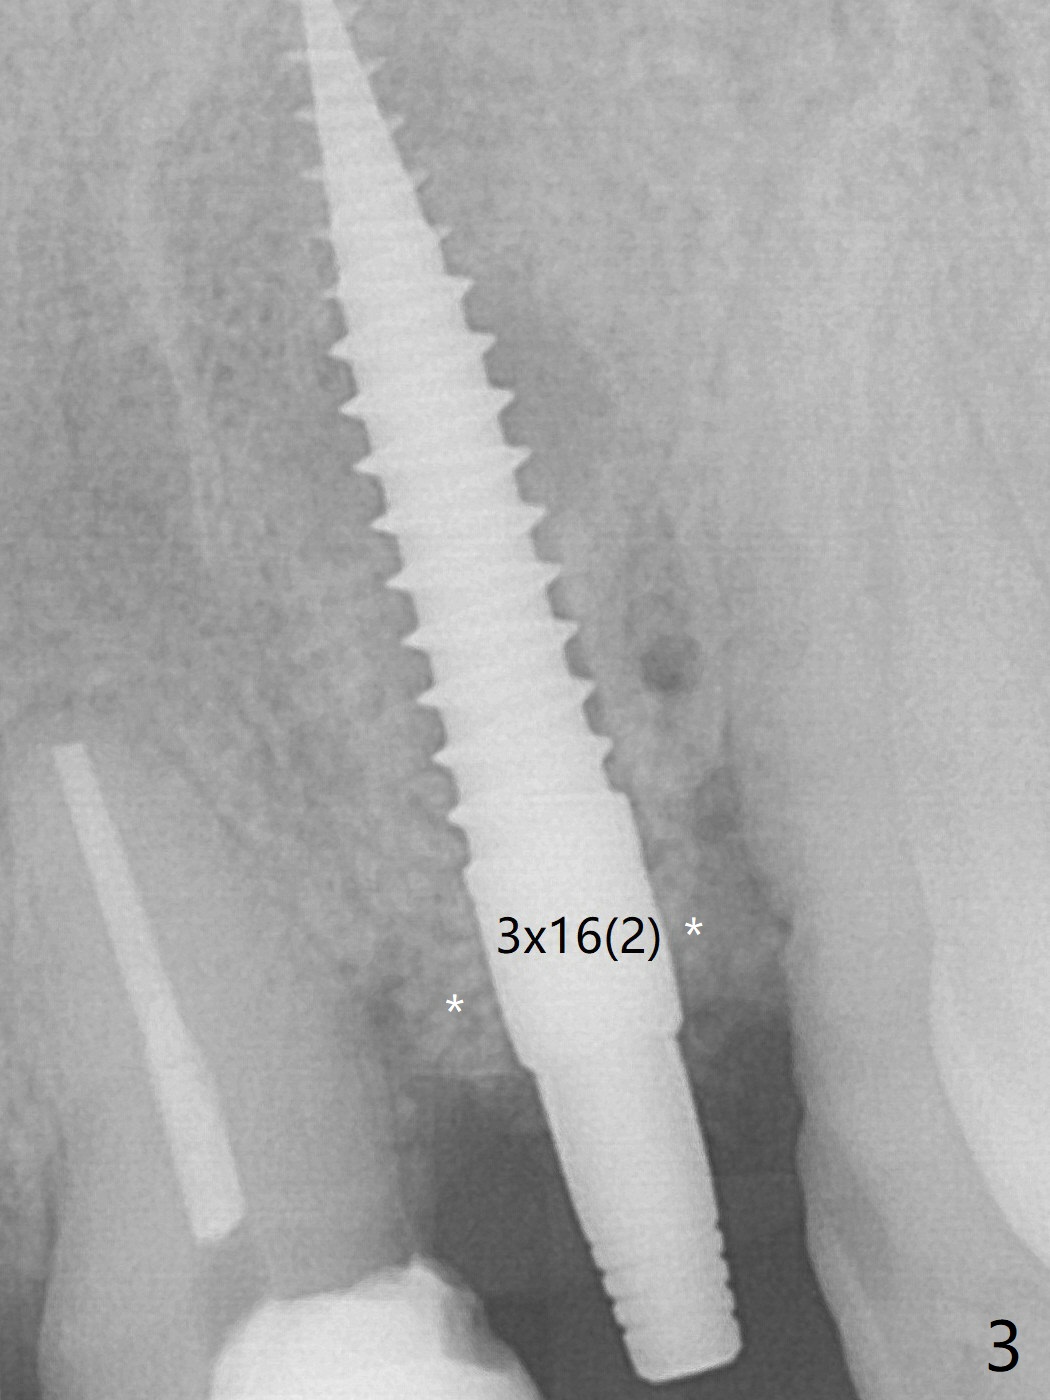

After curettage of the apical granulation tissue, a 3x16(2) mm 1-piece implant is placed with 20 Ncm because of slight overprep using 2 mm drill (Fig.3 (*: allograft)). The density of the bone immediately next to the implant threads increases 6 months postop (Fig.6 *).